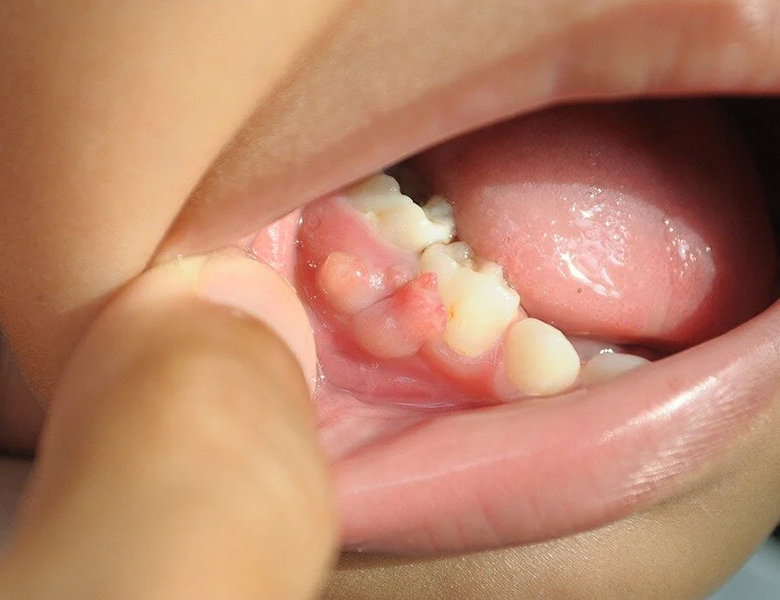

唇や舌の下のぷっくりとした袋(粘液嚢胞)

下唇の裏や舌の裏にできる、直径数ミリ〜1センチ程度の透明、あるいは青紫色の柔らかい膨らみです。

唾液を作る小さな工場(小唾液腺)の出口が、誤って噛んでしまったりすることで詰まり、唾液が組織の中に漏れ出して袋状に溜まったものです。

潰れると一時的に小さくなりますが、数日で再発を繰り返すのが特徴です。

当院の対応

自然に治ることもありますが、再発を繰り返す場合は原因となっている唾液腺を含めた摘出が必要になるため、適切な医療機関をご紹介します。